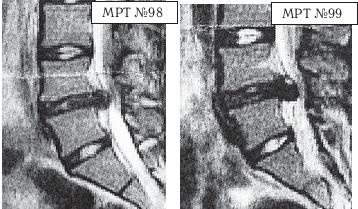

Иллюстрация к книге — Остеохондроз для профессионального пациента [i_117.jpg]

На МРТ № 98 у той же пациентки наблюдается послеоперационный рецидив грыжи межпозвонкового диска в сегменте LIV—LV

На МРТ № 99 у той же пациентки наблюдается рецидив после двух операций, секвестрированная грыжа межпозвонкового диска LIV—LV